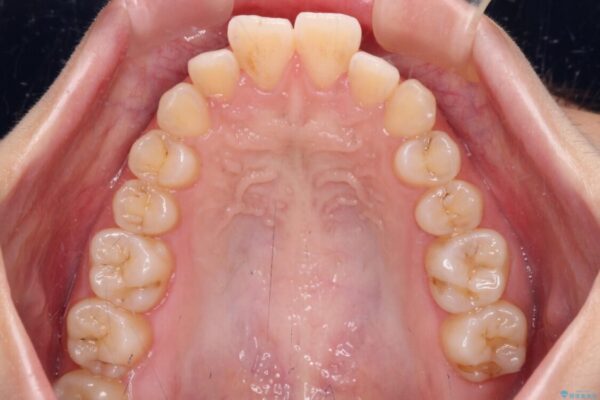

治療後

• 【モニター】口が閉じられない ワイヤー装置での抜歯矯正 治療後画像